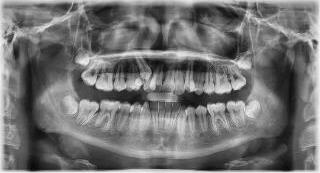

Se presenta una paciente de 29 años con el motivo de consulta “quiero arreglarme los dientes” en los

estudios de inicio se observa en la radiografía lateral de cráneo (Figura 1) clase II esquelética y crecimiento vertical. En los estudios de inicio extraorales en las fotografías de frente y perfil (Figura 2) no muestra exposición dental al momento de sonreír, un perfil convexo y el tercio inferior aumentado respecto al tercio superior y medio de la cara.

Estudios radiográficos de inicio

Al análisis radiográfico (Figura 3) se observa la clase II esquelética, patrón de crecimiento normodivergente, incisivo superior con adecuada inclinación respecto a su base ósea, incisivo inferior ligeramente proinclinado y vías aéreas permeables. En la radiografía panorámica (Figura 4) se ven 33 órganos dentarios OD, el infantil 53 presente en boca, el OD 13 impactado, los 37 y 47 en proceso de erupción y los terceros molares en formación.